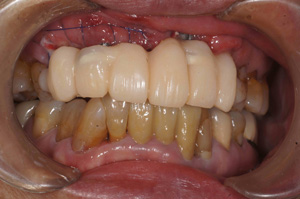

@@R.S‚³‚ñ@56Î —«  ‘åŠw‹³Žö @Žèp“ú@‚Q‚O‚O‚W”N ‚QŒŽ ‚X“úi“yj@㉺Š{  ƒm[ƒxƒ‹ƒKƒCƒhŽg—p@Ö¬“à’ÁÖ@•¹—p@@@

@@@@@ãŠ{  All on ‚U@‘¦Žž‰Ád@@

@@@@@@@@@@@@@ Rpl Tapered Rp  ‚P‚O mm(‚U–{)

@@@@@‰ºŠ{¶‰E@‘¦Žž‰Ád@ ‚R Unit Bridge@

@@@@@@@@@@@ @Rpl Tapered Rp  ‚P‚O mm(‚S–{)@@–ƒWƒ‹ƒRƒjƒAƒNƒ‰ƒEƒ“‚ÅÅI•â’Ô